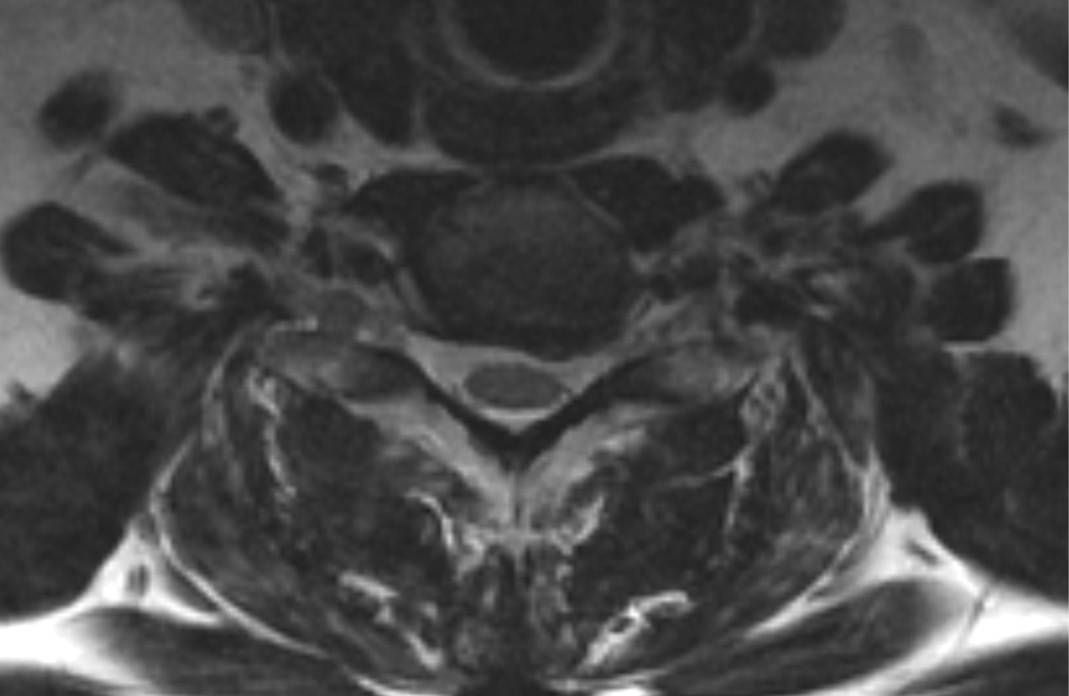

MRIs illustrated mild degenerative disc disease from C4-6 with disc herniations at both C4-5 and C5-6. The axial slice through C4-5 showed a right central disc herniation causing central and mainly right-sided foraminal stenosis. The axial slice through C5-6 showed a central disc herniation also causing central and mainly right-sided foraminal stenosis. The axial slice through C6-7 showed a left-sided disc herniation causing some left-sided foraminal stenosis, however, the patient did not demonstrate any left-sided symptoms.